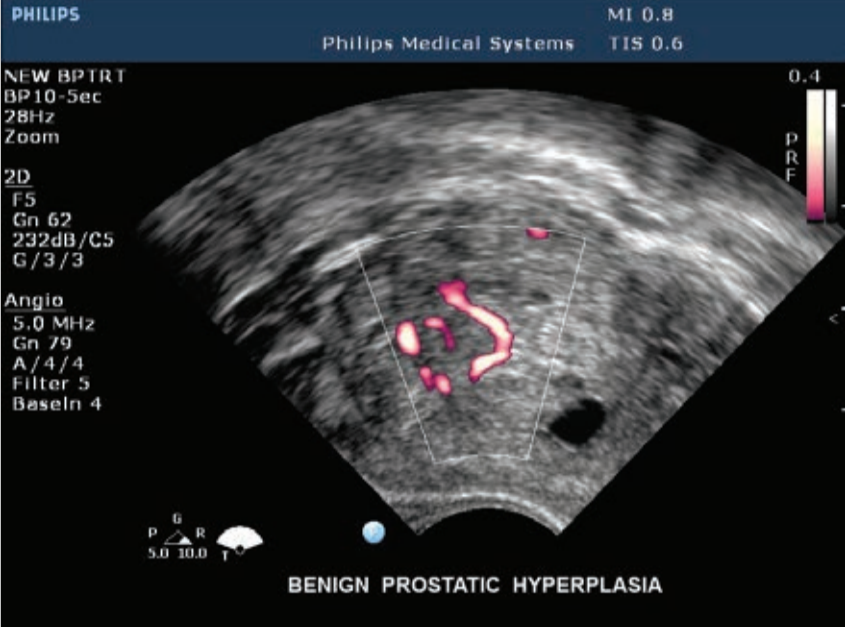

- Gracias a su software de cuantificación QLAB y sus mejoras de configuración específicas de enfermedades cardiovasculares, permite ayudarlo a realizar diagnósticos muchos más rápidos y eficientes.

- El sistema de ecocardiograma iE33 forma parte de la línea de alta gama de ecógrafos Philips.